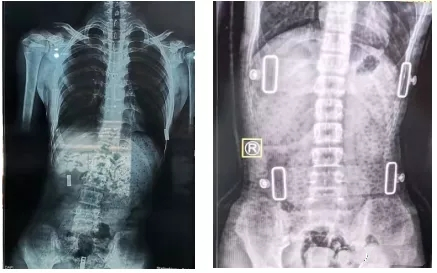

一般我們認為,支具治療3個月后需要進行復(fù)查。復(fù)查時需要脊柱全長正側(cè)位X線片,同時觀察患者支具佩帶區(qū)域皮膚情況。治療過程中如果患者因生長發(fā)育或其他原因造成支具佩戴有不舒服的感覺,需要重新制作支具。支具一般需要持續(xù)佩戴至生長發(fā)育停止,時間隨孩子就診時間以及生長發(fā)育狀況有所不同。

有時戴了支具后脊柱會反方向傾斜。其實,這是因為一般支具治療會采取一種“過度矯正”的方式,以保證脫下支具后身體的反彈更接近于中心線,而不是向原側(cè)彎方向加重。